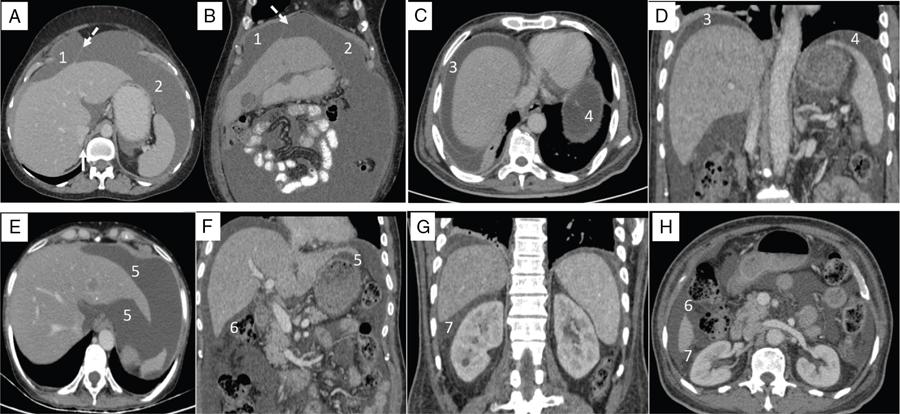

Shivsamb Jalkote, Slesha Bhalja, Disha Lokhandwala, Mansi Jantre, Karthik Ganesan Peritoneum is involved in a diverse group of primary as well as secondary pathologies ranging from the infective/inflammatory spectrum to malignancies. Peritoneal diseases are both common and potentially life threatening, and yet often get neglected in routine evaluation, due to the complex peritoneal anatomy and sometimes subtle imaging manifestations. The radiologist forms an integral part of the multidisciplinary team dealing with peritoneal pathologies and hence, having a lucid understanding of peritoneal anatomy, pathways of disease spread and different treatment options is paramount for an accurate radiological analysis. All three major serosal cavities (pleural, pericardial and peritoneal) of the body are derived from a single coelomic cavity, which is lined by a continuous mesothelium. At 2 weeks of gestational age, during the gastrulation stage, the embryo is a trilaminar disc, composed of the endoderm, mesoderm and ectoderm. During this stage, the development of the coelomic cavity commences as a consequence of morphological changes in the mesodermal cells leading to a coalition of the intercellular spaces. Peritoneum originates from mesoderm with its parietal layer developing from somatic mesoderm and visceral layer developing from splanchnic mesoderm. Initially, the peritoneum is an empty sac into which the growing gut tube protrudes (at 3 weeks of gestational age), resulting in the formation of the dorsal mesentery (formed by the fusion of two layers of the splanchnopleuric mesoderm) by which the gut tube is suspended lengthwise. The mesodermal cells opposed to the gut tube represent the future visceral peritoneum and those lining the body wall and the septum transversum form the future parietal peritoneum. Analogously, the ventral mesentery originates from the mesoderm of the septum transversum with the closure of the anterior abdominal wall, and, is short and not as extensive as the dorsal mesentery. The two mesenteries are aligned in the sagittal plane, subdividing the primitive peritoneum into right and left cavities, which are continuous anteriorly below the inferior edge of the ventral mesentery. With the development of various abdominal organs as buds from the gut tube, the capacity of the abdominal cavity diminishes, pushing the midgut loop into the umbilical cord. This physiologic herniation of the midgut takes place at the 6th week of gestation. Simultaneously, as the peritoneum drapes over the developing organs, there is compartmentalization of the cavity and a pattern of folds develops that eventually form the peritoneal ligaments. The majority of these ligaments arise from the ventral or dorsal mesentery. As the hepatic bud develops within the ventral mesentery, derivatives of the ventral mesentery can be divided based on their relation to the liver. The gastrohepatic ligament (lesser omentum) develops dorsally and the falciform, coronary, and triangular ligaments develop ventral to the liver. Conversely, the dorsal mesentery spans between the gut tube and the posterior abdominal wall, and the spleen and pancreatic tail develop within it. In congruence, it forms the gastrophrenic, gastrosplenic and splenorenal ligaments and peritoneal folds of the small and large intestines. As stated earlier, the dorsal mesentery has a relatively larger caudad extension and since the spleen develops in its upper portion, the rapidly growing mesentery beyond the spleen forms the greater omentum. Finally, the differential growth of the greater curvature of the stomach and the right hepatic lobe results in rotation of the abdominal organs and their mesentery, and the cephalad portion of the peritoneal cavity is divided into a larger ventral cavity, called the greater sac, which caudally communicates with the common peritoneal cavity, and a smaller dorsal cavity called the lesser sac. The key aspects of peritoneal development are summarized in Flowchart 8.6.1 and Fig. 8.6.1. Laparoscopy remains the gold standard in the assessment of peritoneal disease, however, it is an invasive technique, and has certain diagnostic limitations including the inability to assess parenchymal diseases, extraperitoneal diseases, and also has limited utility in the presence of adhesions. Hence laparoscopy is not recommended as the first-line modality and has been replaced by cross-sectional imaging in routine clinical practice. The role of imaging is primarily to assess disease burden in terms of volume and extent and to identify surgically nontreatable disease, which reduces open and shut laparotomies. Peritoneal metastatic disease burden is assessed using peritoneal carcinomatosis index (PCI) both surgically as well as using cross-sectional imaging, details of which will be discussed subsequently. CT, MRI and PET/CT are all commonly used imaging modalities, however, there is no singular universally accepted reference imaging standard for the peritoneal disease. In a recent meta-analysis evaluating the diagnostic performance of imaging in the detection of peritoneal metastasis (PM), authors concluded that MRI (DWI) and PET/CT show comparable diagnostic performance in gastrointestinal and ovarian cancer malignancies however the widespread availability of MRI makes it the more likely imaging modality of choice in the future. The results of this study are summarized in Table 8.6.1. Conventional imaging including radiography and barium studies have a poor diagnostic yield in evaluating peritoneal pathologies. Abdominal radiographs are usually restricted for identifying pneumoperitoneum and bowel obstruction in the setting of acute abdominal pain. Diffuse increase in radio-opacity of the abdomen, poor definition of soft tissue shadows (psoas, liver and spleen), bulging flanks along with medial displacement of small bowel loops from the properitoneal fat stripe are indirect markers of large ascites which can prompt further evaluation with ultrasonography. Indirect features of peritoneal disease on barium studies include mass effect and displacement of adjoining bowel loop, narrowing of bowel loop with bowel dilatation along with nodularity, spiculation, or tethering of adjacent mucosal folds or haustra with sacculation of the uninvolved contralateral border. Barium studies have fallen out of favour in routine radiological practice owing to the widespread use of cross-sectional imaging. Ultrasonography (US) is a readily available and relatively inexpensive imaging tool. Traditionally its role in the evaluation of peritoneal pathologies is limited as US beam gets strongly reflected at the interface of air and visceral structures which leads to obscuration of underlying structures. US remains the primary imaging modality in the evaluation of an acute abdomen and is useful in detecting of ascites, focal lesions and any focal abnormality at the site of tenderness. US has the unparalleled advantage of providing real-time assistance in performing imaging-guided procedures such as paracentesis and peritoneal biopsies. US can be used in characterization of focal lesions (as solid, solid-cystic and cystic) and assessment of internal vascularity using colour Doppler. Transvaginal US provides a good overview of pathologies involving pouch of Douglas besides the uterus and adnexa. Experienced and skilled sonologists can detect omental thickening, peritoneal nodules and small surface deposits using high-frequency transducer (Fig. 8.6.2). Endoscopic US allows assessment of diseases involving peritoneal ligaments besides assistance in a guided biopsy. The reported sensitivity, specificity and accuracy of EUS-FNA versus CT/MRI in detecting PM was 91% versus 28%, 100% versus 85% and 94% versus 47%, respectively. CT is the most commonly employed imaging modality in the evaluation of peritoneal pathologies due to its widespread availability, fast acquisition and high spatial resolution. Current generation multidetector CT scanners (64 slices and above) offer very thin collimation, leading to the acquisition of near isotropic volumetric data which allow reformations in coronal and sagittal images without any added imaging time. It is the modality of choice for preoperative staging in most primary abdominal and pelvic malignancies (e.g. stomach, appendix, ovary) owing to its ability to detect local and regional infiltration, nodal involvement and distant metastases. CT is also used to evaluate PCI and detect disease in critical and occult locations, thus significantly altering further management strategies. CT is the most common imaging modality used in postoperative surveillance and evaluation of postoperative recurrence. CT protocol includes administration of both enteric contrasts (oral and rectal) and intravenous contrast (Table 8.6.2). Optimal bowel distension is key as collapsed loops can mimic disease and also mask the serosal and endoluminal disease. Often, a CT scan of the chest is performed as an adjunct to rule out pleuroperitoneal/transdiaphragmatic dissemination. Helical (≥64 slice scanner) Dual energy scanner if available As thin as possible (≤1 mm) Same as section thickness without gap From xiphisternum to pubic symphysis Chest included if suspicion of thoracic involvement 1 L of positive oral contrast over duration of 60 minutes and 500 mL of positive rectal contrast on table before administration of IV contrast 1.5–2 mL/kg of nonionic contrast with high iodine concentration (≥ 300) at rate of 3–5 mL/sec Unenhanced imaging not recommended. Monophasic acquisition at 60 seconds usually sufficient in majority cases Arterial phase at 20 seconds acquired for arterial assessment Delayed phase in cases of ureteric obstruction, slow bowel transit and suspected leak. Axial 1 mm thickness, multiplanar reformats in coronal and sagittal planes at 1 mm MIP or 3D volumetric sections for vascular assessment There is a wide range of reported diagnostic accuracy (sensitivity ranging from 25% to 100%, specificity ranging from 78% to 100%) of CT in the assessment of PM depending on the expertise of the reader and scanner type. In general, key factors affecting CT sensitivity include the size of lesion, the region of affection and presence of ascites. 64 slice scanners with multiplanar reformations allow 100% sensitivity and positive predictive value in detecting lesions measuring >5 cm, which partly diminishes for lesions between 0.5 cm and 5 cm in size with sensitivity and positive predictive being 83% and 93%, respectively. It receives the most criticism in the evaluation of lesions < 0.5 cm with significantly low sensitivity and positive predictive value (43% and 76%, respectively). There is also a great degree of variation in sensitivity based on the anatomical location of the disease. In a study by Koh et al., the detection rates ranged from 8% to 67%, depending on the region involved; only the epigastrium exceeded 60%, with the small-bowel disease being the most poorly visualized (8%–14%). The sensitivity for tumour detection in epigastrium, greater omentum and under surfaces of the diaphragms was 60%–90%, while it was 50%–70% in the retroperitoneum and pelvis, and small bowel-mesentery involvement was detected in merely 20%–50% of cases. These are noteworthy findings, as small-bowel involvement has major implications on outcome and is one of the limiting factors for complete cytoreduction. Poor soft tissue resolution of CT doesn’t allow accurate differentiation between mucinous deposits from ascites. Administration of positive enteric contrast can mask calcified serosal deposits. DECT uses two separate x-ray energy spectra and allows characterization of tissues based on their differences in attenuation properties at different energies. Though the role of DECT in the assessment of abdominal pathologies is increasingly reported in the literature, there are very limited data available on its application in assessment of peritoneal pathologies. The combination of iodine overlay with conventional imaging has shown a better specificity in differentiating PM from benign peritoneal entities, and hence can be particularly useful in the postoperative setting. MR imaging offers excellent soft tissue resolution, multiplanar capabilities and avoids exposure to ionizing radiation, making it an attractive tool for evaluation of peritoneal diseases. MRI is better suited and can be problem solving in visualization of smaller lesions (<1 cm) and assessment of relatively concealed areas such as subphrenic, mesenteric and bowel serosa. Unenhanced T1- and T2-weighted images can show larger peritoneal deposits and masses but are relatively insensitive for the depiction of smaller lesions. The combination of diffusion-weighted imaging (DWI) and delayed gadolinium-enhanced MR imaging is considered the most accurate technique for detecting peritoneal tumours (Fig. 8.6.3). MRI protocol for assessment of peritoneum has been detailed in Table 8.6.3. In a study by Low RN et al., MRI PCI correctly categorized tumour volume in 91% of patients compared to surgical PCI, as opposed to 50% with CT. In addition, MRI demonstrated per site sensitivity of 95%, specificity of 70% and accuracy of 88%, while CT showed a corresponding per site sensitivity of 55%, specificity of 86% and accuracy of 63%. MRI PCI has also shown to have better prediction of intraoperative burden of disease for invasive appendiceal and peritoneal mesothelioma histologies as compared to CT-PCI. *This general imaging protocol is based on 3 T MRI Siemens system, covers both abdomen and pelvis. Protocol is modified depending on primary disease and type of scanner. Low RN. Preoperative and surveillance MR imaging of patients undergoing cytoreductive surgery and heated intraperitoneal chemotherapy. Journal of gastrointestinal oncology. 2016 Feb;7(1):58. The higher cellularity of majority of peritoneal nodules results in restriction of water movement and corresponding high signal intensity on DW images. On the higher b-value images, bowel contents are suppressed and the serosal and peritoneal tumours become hyperintense. DWI is also useful to demonstrate associated lymphadenopathy, hepatic and osseous metastases. In a study by Zhang et al., in PC of colorectal carcinoma, DWI demonstrated sensitivity of 69.4%, 91.3% and 100% for lesions measuring <0.5 cm, 0.5–5.0 cm and >5 cm, respectively. The overall sensitivity, specificity and accuracy of DWI for the detection of peritoneal tumours were 80.3%, 84.5% and 82.1%, respectively. DWI/MRI is also superior in demonstrating lesions involving small bowel wall, with an accuracy of 92%–95% versus 48% for CT. Reported negative predictive value of DWI for small bowel serosal metastases is 100%. Whole-body DWI/MRI was highly accurate for the prediction of inoperability (PPV 100%, NPV 90.3%) and was capable of detecting metastases both inside and outside the abdominal cavity. Peritoneal tumours enhance slowly and are best depicted on the final set of images obtained about 5 minutes following gadolinium administration. The increased conspicuity of these enhancing peritoneal tumours improved detection of small tumours that are often missed on CT scans. For this reason, perfect breathhold is essential while obtaining the final set of images and if images are acquired later, contrast that has diffused into the ascitic fluid can obscure smaller lesions. The high-contrast conspicuity of fat-suppressed and delayed gadolinium-enhanced MRI makes it the imaging modality of choice in depicting subcentimetre deposits (including those measuring <5 mm), and also deposits in anatomically concealed sites (e.g., subphrenic, mesenteric and bowel serosa). Gadolinium-enhanced MRI has higher sensitivity in detecting peritoneal lesions <1 cm which is about 85%–90% compared to 22%–33% for CT. Despite the clear superiority of MRI over CT, the major detractors against MRI are the long exam times and the higher expense burden. Longer acquisition times can lead to motion artefacts related to respiration and bowel peristalsis compromising detection of smaller lesions. MRI is contraindicated in patients with pacemakers, cochlear implants and claustrophobic patients with some exceptions. DW-MRI is less sensitive in special histological subtypes such as signet ring cell and mucinous adenocarcinoma due to their limited restricted diffusion. The combined use of FDG-PET with anatomical CT imaging, provides the added benefit of qualitative and semiquantitative metabolic analysis (Fig. 8.6.4). PET/CT has an established role in staging of most of the primary tumours of the chest, abdomen and pelvis. It is also helpful in assessing malignant ascites or PM of an unknown primary. In disseminated malignancies, it can localize the optimal site for biopsy depending upon metabolic activity of the lesion. PET/CT should be used selectively in preoperative assessment of patients with large tumour volumes and poor prognostic histologies being considered for CRS and HIPEC to rule out extra abdominal metastases. It can also detect extraabdominal metastases, including mediastinal and supraclavicular nodes, and other organ sites, such as bone and brain. It can also detect nodal involvement in normal-sized lymph nodes seen on conventional cross-sectional imaging. PET/CT also plays a role in disease surveillance and assessment of response to neoadjuvant chemotherapy. This is particularly relevant in malignancies where anatomical changes are so small that measurement of size change alone becomes unreliable and also in differentiating between residual/recurrent disease and postoperative changes after CRS and HIPEC. Besides oncological indications, PET/CT is also helpful in assessment of benign and inflammatory diseases to evaluate disease extent and also localize the site for biopsy. In cases of pyrexia of unknown origin, PET/CT has often been employed to demonstrate unsuspected peritoneal disease. Utility of PET/CT in peritoneal disease assessment is limited in developing counties due to its higher cost burden and lower accessibility. Certain histological subtypes such as mucinous and signet ring cell carcinomas show low FDG uptake making PET/CT less sensitive. Low metabolic uptake in these subtypes is thought to be due to low tumour cell density, higher content of metabolically inert mucin and lack of expression of glucose transporter Glut-1. This is more relevant in context of colorectal malignancy where mucinous carcinoma and signet ring cell carcinoma more frequently metastasize to the peritoneum compared to adenocarcinoma (48%, 51% and 20%, respectively). PET/CT is prone to artefacts caused by misregistration between the CT and PET images which can lead to inaccurate assessment of certain regions such as dome of diaphragm and structures adjoining the urinary bladder, making the detection of pelvic implants difficult due to partial volume effects. Implants against the small bowel and mesentery may be obscured by the physiological metabolic activity of bowel. Pretreatment PET/CT demonstrates a higher accuracy than CT for nodal and metastasis staging but has limited sensitivity to detect PM, especially when there is small-volume disease as only 13.6% of the nodules less than 0.5 cm were correctly identified by PET/CT. Table 8.6.4 summarizes role of different imaging modalities for assessment of peritoneal diseases. Peritoneum is the largest serosal membrane in human body with surface area of about 2.2 m2. It is composed of parietal and visceral layers which are continuous with each other, with parietal peritoneum lining the coelomic cavity and visceral peritoneum lining the visceral organ (Fig. 8.6.5). The peritoneum essentially minimizes friction, resists infection and stores fat, allows free movement of the abdominal viscera which gets restricted in presence of adhesions. Peritoneum acts as first line of defence in controlling disease spread, and, it exudes fluid and cells in response to injury or infection (peritonitis), to wall off or localize infection. In natural states, intraperitoneal spread of infection is limited by lymphoid aggregates and stomata on both the peritoneal layers. Omentum is commonly known as policeman of abdomen as it migrates to the site of infection and isolates affected area from healthy tissues. Iatrogenic violation of peritoneum following surgery can lead to recurrence along the operative incision scar sites and along the vaginal cuff following hysterectomy in pelvic malignancies. The parietal peritoneum is supplied by nerves (e.g. phrenic and thoracoabdominal) to the adjacent body wall, and is predominantly very sensitive to pain, which explains the typical referred shoulder pain from upper abdominal pathologies such as gall stones and pancreatitis. The visceral peritoneum is insensitive to pain and responds mainly to stretching. These two layers encompass a potential space, called the peritoneal cavity which contains approximately 50–75 mL of clear serous fluid. Peritoneal cavity is a closed space in males while in females it communicates with extraperitoneal pelvis through ostia of fallopian tubes allowing transport of ovum. This communication serves as natural route for ascending spread of sexual transmitted disease from genital organs into peritoneal cavity leading to pelvic inflammatory disease and uncommonly perihepatitis (Fitz–Hugh–Curtis syndrome). The invaginations of the peritoneum result into formation of three different types of structures namely ligaments, omentum and mesentery (Figs. 8.6.6–8.6.9) which serve as bridges that permit blood, lymph vessels and nerves to reach the viscera. Ligaments are double folds of peritoneum that connect one organ to another organ or to the abdominal wall and are named usually after the respective viscera. The liver, for example, is connected to the diaphragm by the falciform ligament, coronary ligament and right and left triangular ligaments. Mesenteries are double folds of peritoneum that suspend intestine to the posterior abdominal wall (retroperitoneum) such as the small bowel mesentery, transverse and sigmoid mesocolon. Omentum are double folds of peritoneum that extends from the stomach to other organs and include the greater and lesser omentum. Table 8.6.5 summarizes the peritoneal ligaments in abdomen and pelvis. In medical school days, the anatomy textbooks traditionally divided abdomen and pelvis into tricompartmental model comprising of peritoneal cavity, retroperitoneum and extraperitoneal spaces. This model is good for basic understanding of anatomy and confinement of certain disease processes but fails to explain spread of diseases from retroperitoneum to peritoneum besides spread of some disease processes within peritoneal cavity itself. Considering these shortcomings of conventional description of anatomy, the unifying concept of subperitoneal space has evolved in literature and is getting accepted increasingly. As per this concept, abdomen and pelvis are divided in two spaces peritoneal cavity and subperitoneal space which are separated from each other by peritoneum. Subperitoneal space (Fig. 8.6.10) is large anatomically continuous potential space which connects peritoneal cavity with retroperitoneum. It constitutes the subserosal areolar tissue and fat tissue lining the inner surfaces of the peritoneum and the abdominopelvic musculature. The omentum, ligament and mesentery are the interconnecting peritoneal folds building the subperitoneal space. All the abdominal and pelvic organs along with their vascular, lymphatic and nervous supplies are situated within subperitoneal space. With this concept, we want to correct the common misconception of intraperitoneal organs as in strict terminology there is no organ within the peritoneal cavity itself. It is imperial to understand differences between peritoneal and subperitoneal spaces as these are mutually exclusive spaces having distinct patterns of disease spread which we will discuss in subsequent sections. In resting state, peritoneal cavity is collapsed and thus not visible on routine imaging. Peritoneal cavity usually gets distended due to disease processes composed of fluid, air or masses. The peritoneal cavity is divided into two parts: the greater sac and the lesser sac which communicate with each other via an epiploic foramen (of Winslow). The greater sac forms main peritoneal cavity and extends from the diaphragm down into the pelvis. The lesser sac is small diverticulum and lies between stomach and pancreas. For better understanding, abdominal peritoneal cavity is divided into supra- and inframesocolic compartments, communicating with pelvic peritoneal cavity which is further divided by other peritoneal folds and reflection (Flowchart 8.6.2, Figs. 8.6.10 and 8.6.11). Supramesocolic compartment (Fig. 8.6.12) is situated between the diaphragm and transverse mesocolon. It is arbitrarily divided into right and left supramesocolic peritoneal spaces, which can be further subdivided into a number of subspaces by upper abdominal organs and peritoneal ligaments. Right supramesocolic space is divided into three subspaces: right subphrenic space, right subhepatic space and lesser sac. Right subphrenic space is partially separated from right subhepatic space by right triangular ligament. Right subphrenic space is situated between right hemidiaphragm and right lobe of liver (superior, anterior and right lateral surfaces). It is limited posteriorly by the coronary ligament and medially by the falciform ligament with the latter separating it from the left subphrenic space. Right subhepatic space is situated inferior to right lobe of liver and has anterior and posterior components. Anterior component is limited inferiorly by transverse mesocolon whereas the posterior component extends anterior to right anterior perirenal fascia. Posterior component of right subhepatic space is commonly known as hepatorenal pouch (of Morrison) and forms most dependent site in supine position, thus being a common site of fluid accumulation. The right subhepatic space freely communicates with right subphrenic space superiorly and right paracolic gutter inferiorly. Lesser sac (also known as omental bursa) is situated superior to the transverse mesocolon, anterior to pancreas and posterior to the lesser omentum, stomach and gastrocolic ligament. Lesser sac (Fig. 8.6.13) communicates with right subhepatic space (of greater sac) via epiploic foramen which is bounded by IVC posteriorly, free margin of hepatoduodenal ligament anteriorly, D1 (first part of duodenum) caudally and caudate lobe of liver rostrally. Division of lesser sac into smaller superior compartment (superior recess) and larger inferior compartment (inferior recess and splenic recess) is accomplished by prominent crescentic gastropancreatic fold (peritoneal fold overlying common hepatic and left gastric artery) which extends from neck of the pancreas to the upper part of lesser curvature of stomach. The superior recess is situated to the right of midline above pancreas and posterior to lesser omentum. It surrounds the medial aspect of the caudate lobe and superiorly into the fissure for the ligamentum venosum. Splenic recess extends to splenic hilum, and is limited by gastrohepatic ligament (anterior), gastrosplenic ligament (lateral) and splenopancreatic ligament (posterior). Inferior recess is located to left of midline, separates stomach from the pancreas and transverse mesocolon. In few cases, an infrapancreatic part can be seen due to persistence of inferior recess within the greater omentum or due to downward bowing of transverse mesocolon. Left supramesocolic space is wider than right supramesocolic space and is limited above by left hemidiaphragm and below by transverse mesocolon and phrenicocolic ligament. Left supramesocolic space (subphrenic part) is medially separated from right supramesocolic space by falciform ligament and inferiorly from left paracolic gutter by phrenicocolic ligament. It is divided into four communicating subspaces: anterior left subphrenic space, posterior left subphrenic space, anterior left perihepatic space and posterior left perihepatic space. All these spaces communicate with each other. The definitions of the boundaries of these spaces vary in literature. Anterior left subphrenic space is situated between gastric fundus and left hemidiaphragm. Posterior left subphrenic space (also known as perisplenic space) surrounds spleen. Anterior left perihepatic space is situated between anterosuperior aspect of left lobe of liver and left hemidiaphragm. Posterior left perihepatic space (also known as gastrohepatic recess) is situated between inferior aspect of left lobe of liver and lesser omentum. Inframesocolic compartment (Fig. 8.6.14) extends below transverse mesocolon to the level of pelvic brim and is divided into large central part and smaller paracolic part (lateral recesses). Central portion of inframesocolic compartment is unequally divided by obliquely oriented small bowel mesentery leading to formation of smaller right inframesocolic compartment and larger left inframesocolic compartment. Right inframesocolic space terminates at the ileocaecal junction and does not communicate with pelvis. Left inframesocolic space is in communication with pelvic peritoneal spaces except at the sigmoid mesocolon attachment which offers partial barrier. Peritoneal recesses on the posterior abdominal wall lateral to the ascending and descending colon form right and left paracolic gutters respectively. Both paracolic gutters communicate freely with pelvic peritoneal spaces. Right paracolic gutter is deeper than left gutter and is in free communication with right supramesocolic space. Left paracolic gutter is partially limited from left supramesocolic space due to presence phrenicocolic ligament. Pelvis constitutes about one-third of the total volume of the peritoneal cavity and is most dependent part in both supine and erect positions. Inferiorly peritoneum drapes over fundus of urinary bladder, anterior and posterior surface of uterus and upper posterior vagina in females and anterolateral surface of the upper rectum leading to formation of different peritoneal spaces. The urinary bladder subdivides pelvis into anterior and posterior paravesical spaces. The anterior paravesical space is further compartmentalized by remnant of the urachus (median umbilical ligament), the obliterated umbilical arteries (medial umbilical ligament), and the lateral umbilical ligaments (inferior epigastric vessels) into five fossae: the right and left lateral and medial inguinal fossae and the supravesical fossa. The supravesical space is seen in midline with medial and lateral inguinal fossae placed on either side. The supravesical space lies above urinary bladder between the two medial umbilical folds, is usually occupied by small bowel loops and fundus of distended urinary bladder. Just lateral to the supravesical space is the medial inguinal fossa, located between the medial and lateral umbilical folds. The femoral ring is located inferolaterally and hence ascitic fluid in the medial inguinal fossa can extend into the femoral canal. Finally, the lateral inguinal fossa is located between the lateral umbilical fold and parietal peritoneum (which reflects over the vas deferens or round ligament). It usually contains the cecum or ileum on the right and sigmoid colon on the left. Extension of ascitic fluid into the inguinal canal can occur through the deep inguinal ring, located anteromedial to the lateral inguinal fossa. The posterior paravesical space is a larger recess situated between the urinary bladder and rectum. In women, uterus further divides it into smaller vesicouterine and larger rectouterine spaces. The vesicouterine space is located between the urinary bladder and uterus and is formed as the peritoneum drapes the uterine body and fundus and then runs over the urinary bladder (along its posterosuperior surface). It is continuous with the supravesical space anteriorly and its depth varies with the degree of urinary bladder distension. The rectouterine pouch (of Douglas) is delimited anteriorly by the uterus and broad ligaments and posteriorly by the rectum. Lateral to this cul-de-sac on either side are the uterosacral ligaments that run from the sacrum to the uterine cervix that separate the rectouterine pouch from the laterally located ovarian fossae. In men, the rectovesical pouch is formed as the peritoneum runs from the rectum to the posterior surface of the bladder. Posteriorly, the peritoneal reflection from the upper rectum runs to the pelvic sidewalls, forming right and left pararectal fossae, which vary in size with the degree of rectal distension. Analogous to the uterosacral ligaments in women, the rectovesical space is restricted by sacrogenital folds on either side, which extend from the urinary bladder to the sacrum. The rectovesical space and rectouterine space (pouch of Douglas) form most dependent areas in both in supine and standing positions in males and females, respectively (both in supine and standing positions). The key aspects of pelvic peritoneal spaces are summarized in Flowchart 8.6.3, Figs. 8.6.15 and 8.6.16. Peritoneal recesses represent small pockets or fossae in the peritoneal cavity bounded by folds of peritoneum and possibly represent developmental aberrations. Knowledge of these recesses is important as they can serve as pathways for internal hernias. Multiple peritoneal folds may surround fourth part of duodenum (D4) and duodenojejunal junction forming duodenal recess. Six major duodenal recesses include superior, inferior, paraduodenal, retroduodenal, duodenojejunal and mesentericoparietal recess. The superior duodenal recess is situated to the upper left side of fourth part of duodenum (D4) behind the superior duodenal fold at L2 level. Inferior mesenteric vein is situated behind lateral end of superior duodenal fold. Inferior duodenal recess is situated on left of D4 below DJ flexure and behind the inferior duodenal fold at L3 level. Inferior duodenal recess often exists in association with superior duodenal recess. Reported incidence of superior and inferior duodenal recesses is about 40%–50% and 70%–75%, respectively. Paraduodenal recess is seen on left side and slightly behind D4 bounded anteriorly by paraduodenal (falciform fold). Right free margin of paraduodenal fold contains the inferior mesenteric vein and an ascending branch of the left colic artery. This recess is seen in about 2%–3.8% cases and is site for left paraduodenal hernia. Retroduodenal recess as the name suggests situated behind the third and fourth parts of the duodenum and in front of abdominal aorta. Its orifice is bounded anteriorly by duodenoparietal fold. Retroduodenal space is largest among all the duodenal recesses and is seen in about 2.5% cases. Duodenojejunal recess is situated between the duodenojejunal flexure and root of transverse mesocolon, hence also known as mesocolic recess. Its boundaries include pancreas (superior), left renal vein (inferior) and left kidney (left). Its opening lies between two peritoneal folds, is directed inferiorly and to the right. Duodenojejunal recess is seen in about 20% cases and is almost never associated with other duodenal recesses. Mesentericoparietal recess is situated below third part of duodenum and behind the upper part of the mesentery. Its opening is bounded anteriorly by the fold of mesentery raised by the superior mesenteric artery. This recess is most rare among all with incidence of about 1%. It is the site for right paraduodenal hernia. The key aspects of duodenal recesses are summarized in Table 8.6.6 and Fig. 8.6.17. Peritoneal folds adjoining cecum result in formation of four main recesses: superior ileocaecal recess, inferior ileocaecal recess, retrocaecal recess and paracolic recess (Fig. 8.6.18). Surgically these recesses are important as they can be sites for internal herniation (except for paracolic sulci) or site of abscess formation in complicated appendicitis. Superior ileocaecal recess is bounded in front by the vascular fold of the cecum (containing anterior caecal vessels), behind by the ileal mesentery, below by the terminal ileum and on the right by the ileocaecal junction with its opening on left. Inferior ileocaecal recess is bounded in front by the ileocaecal fold (bloodless fold of Treves), above by the terminal ileum and its mesentery, to the right by the caecum, and behind by the upper part of the mesoappendix with its opening on left. Retrocaecal recess is bounded in front by posterior wall of cecum (and sometimes the proximal ascending colon), behind by the parietal peritoneum (posterior abdominal wall), and on either side by two caecal folds (parietocolic folds). Retrocaecal recess is largest among all the caecal recesses with its opening inferiorly and often contains appendix. Paracolic sulci represent variable one or more shallow lateral depressions in the peritoneum investing the cecum usually within the right paracolic gutter. This recess lies behind and inferior to the apex of inverted V-shaped root of sigmoid mesocolon with orifice opening inferiorly. Posteriorly, it is limited by parietal peritoneum of covering the left ureter at its iliac vessel crossing. This recess can be variable in size ranging from dimple to a small fossa in majority of the cases usually admitting little finger. It forms most common site of sigmoid mesocolon hernia. It can also be involved by peritoneal fluid and metastatic disease. Peritoneal and subperitoneal spaces are mutually exclusive spaces having distinct patterns of disease spread. Different pathways of the intraabdominal and extraabdominal disease spread are summarized in Table 8.6.7.

Computed tomography (CT)

Limitations of CT in the assessment of peritoneal disease